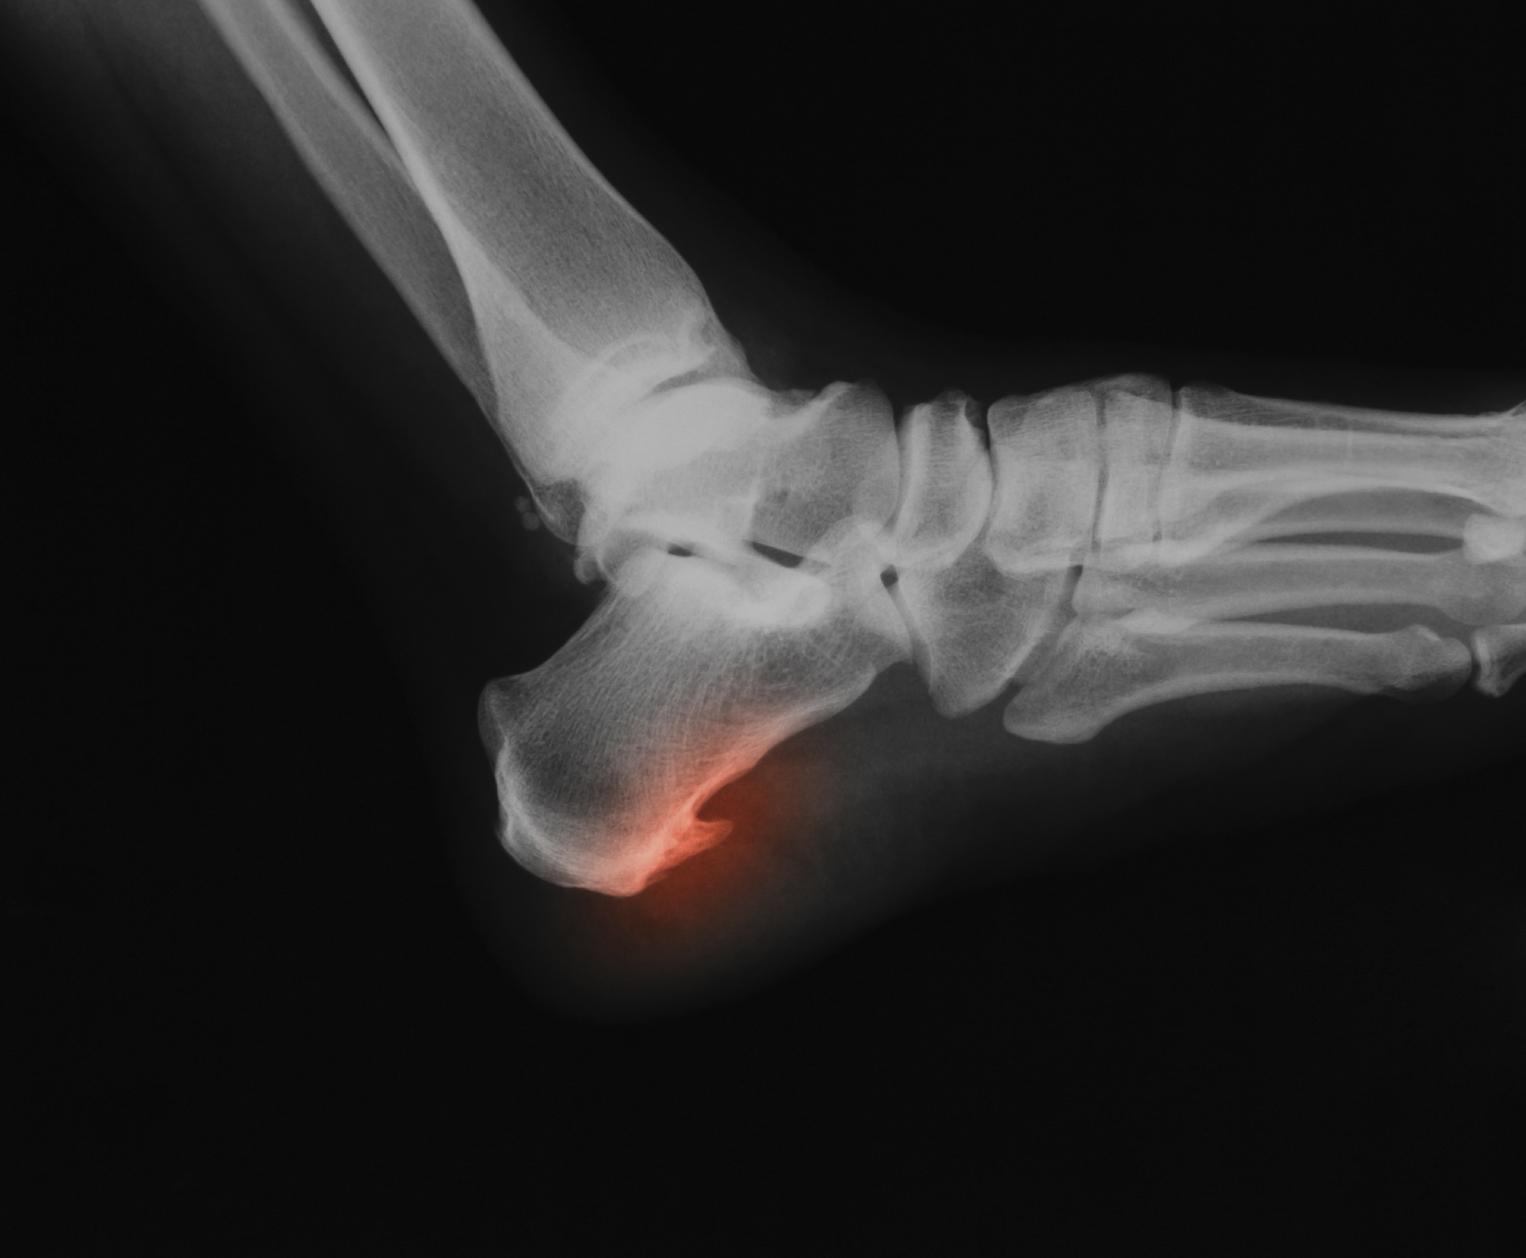

Algunos remedios caseros como el vinagre de manzana, el jengibre, el hielo o los aceites esenciales pueden ayudarnos a aliviar y curar un espolón calcáneo de forma natural y sin tener que recurrir a la cirugía, aunque esto dependerá de la gravedad del caso y de las indicaciones médicas. Un espolón es una calcificación en el talón que suele ocasionar dolor intenso a quienes lo padecen. Aunque realmente es necesario visitar un médico para tratar el espolón y llegar a eliminarlo, para reducir el dolor y facilitar la cura de este problema puedes usar remedios. En este artículo de unCOMO te explicamos cómo curar un espolón con remedios caseros.